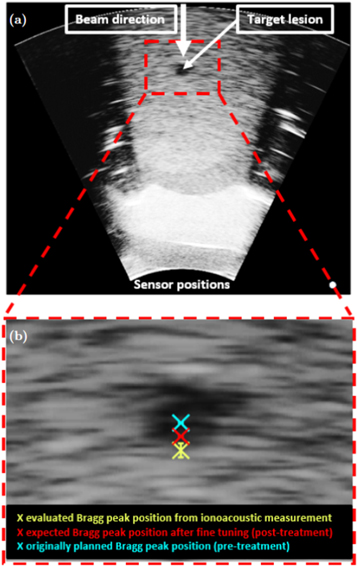

Standard image High-resolution imageThe calibration time is indicated in blue and Pδ (t) as evaluated from the ionoacoustic measurement with 126 MeV protons (see figure 8) is shown in black, while its maximum position is indicated by the black dashed line. Their temporal difference is calculated to be ΔtL = 0.80 μ s ± 0.07 μs, where the indicated uncertainty was calculated in equation (6). This temporal difference is converted to a difference in distance according to equation (9) yielding a spatial offset between the Bragg peak and the calibration location of ΔxL = 1.23 ± 0.10 mm. This spatial offset is used to mark the Bragg peak position in the ultrasound image showing the irradiated region of the phantom using the integrated scale bar intrinsic to every ultrasound image (see figure 14).

Figure 14. The ultrasound image showing the irradiated region of the CIRS phantom highlighting the target lesion (a). Additionally the beam direction and the sensor positions are indicated. The red dashed line shows an inlay which is zoomed in (b). It shows the target lesion with the originally planned Bragg peak position (blue), the expected Bragg peak position after fine tuning the SPR (see section 2.1.2) and the evaluated Bragg peak position (yellow) with the error bars indicating the standard deviation found for a dose of 1.2 Gy.

Download figure:

Standard image High-resolution imageThe same argument as in the calibration holds: While there are a variety of different speeds of sound present in the abdominal phantom which each affect the arrival time of the ionoacoustic signal, the same speeds of sound affect the image generation from the ultrasound probe leading to a stretched or compressed display of the involved media in the ultrasound image. The Bragg peak position can thus be marked as if it would be visible in the ultrasound image, using the ionoacoustic sensor as a low-frequency extension of the ultrasound probe. The ultrasound image including the evaluated Bragg peak position is shown in figure 14.

Panel (a) shows the whole ultrasound image indicating the beam direction, the target lesion and the sensor position. The contrast of the image has been increased to make the target lesion more visible. This is the reason why the image looks overexposed in certain areas. The region indicated by the red rectangle is enlarged in (b) showing the evaluated Bragg peak position from the ionoacoustic measurement (yellow). Additionally, the originally planned Bragg peak position (blue) and the expected Bragg peak position after fine tuning the SPR within the irradiation planning process (red) are marked. The error bar in the measurement is given by the standard deviation of the individual measurements at 1.2 Gy (0.52 mm).

Assuming that the expected Bragg peak position (red) is the ground truth, there is a deviation of approximately 1.0 mm between the expected Bragg peak position and the measured Bragg peak position, which cannot be entirely explained by the statistical uncertainty of the measurement. Nonetheless a Bragg peak localisation with an accuracy of 1.0 mm relative to the anatomy is a substantial reduction to the typical range uncertainties in proton therapy, which are between 1 and 8 mm depending on the tumour (Paganetti 2012).